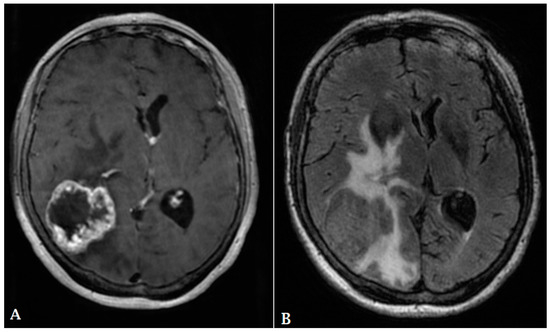

- Mangla, R.; Singh, G.; Ziegelitz, D.; Milano, M.T.; Korones, D.N.; Zhong, J.; Ekholm, S.E. Changes in relative cerebral blood volume 1 month after radiation-temozolomide therapy can help predict overall survival in patients with glioblastoma. Radiology 2010, 256, 575–584. [Google Scholar] [CrossRef]

- Young, R.J.; Gupta, A.; Shah, A.D.; Graber, J.J.; Chan, T.A.; Zhang, Z.; Shi, W.; Beal, K.; Omuro, A.M. MRI perfusion in determining pseudoprogression in patients with glioblastoma. Clin. Imaging 2013, 37, 41–49. [Google Scholar] [CrossRef] [PubMed]

- Hu, L.; Baxter, L.; Smith, K.; Feuerstein, B.; Karis, J.; Eschbacher, J.; Coons, S.; Nakaji, P.; Yeh, R.; Debbins, J.; et al. Relative cerebral blood volume values to differentiate high-grade glioma recurrence from posttreatment radiation effect: Direct correlation between image-guided tissue histopathology and localized dynamic susceptibility-weighted contrast-enhanced perfusion MR imaging measurements. Am. J. Neuroradiol. 2009, 30, 552–558. [Google Scholar] [PubMed]

- Patel, P.; Baradaran, H.; Delgado, D.; Askin, G.; Christos, P.; Tsiouris, A.J.; Gupta, A. MR perfusion-weighted imaging in the evaluation of high-grade gliomas after treatment: A systematic review and meta-analysis. Neuro-Oncol. 2016, 19, 118–127. [Google Scholar] [CrossRef]